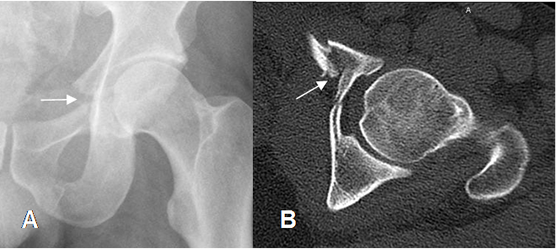

Fig 41. Trauma de pelvis. Compresión AP.

A: Rx AP. Interrupción de la línea ilioisquial, por fractura.

B: TAC axial. Fractura del ramo iliopúbico.